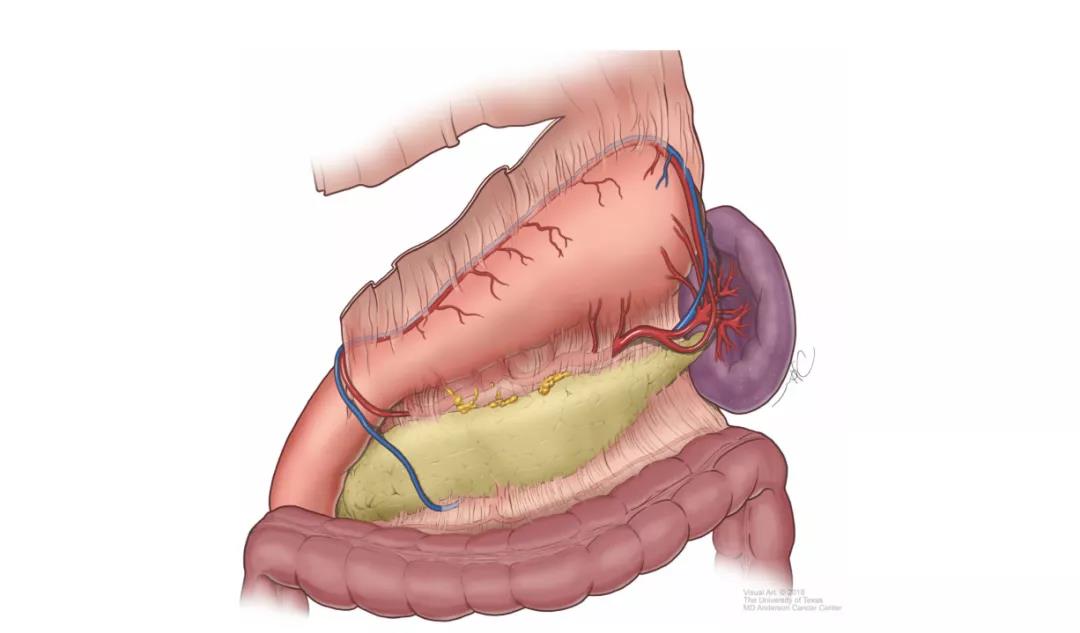

胰腺癌的发病率在世界范围内呈持续上升态势。2021年统计数据显示,在美国所有恶性肿瘤中,胰腺癌新发病例男性居第10位,女性居第9位,占恶性肿瘤相关病死率的第4位。...